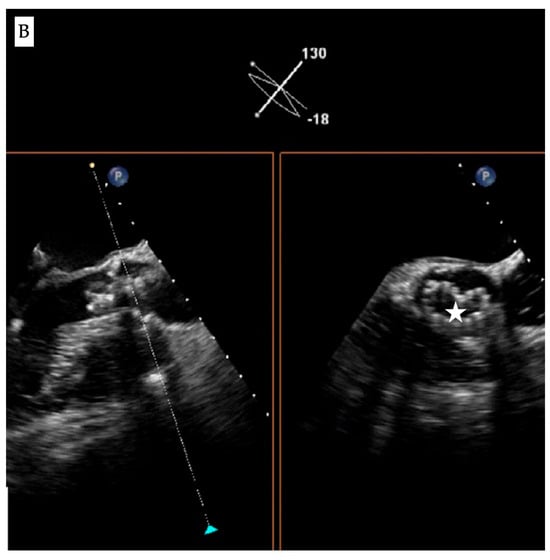

Fluoroscopic and echocardiographic appearance of TAVI infolding. (A) Visual clues for recognizing this complication include a dense vertical line across the valve frame (white arrow) and the inability to reach the intended valve expansion. (B) Short axis window in echocardiography revealing the “Pac man” sign (white star).

Accordingly, evaluation of the bio-prosthesis in two orthogonal views or performing a c-arm fluoroscopic rotation is recommended to identify such complications. Infolding can also be confirmed by echocardiography through visualization of the “Pac-man” sign in the short axis view [] (Figure 1B).